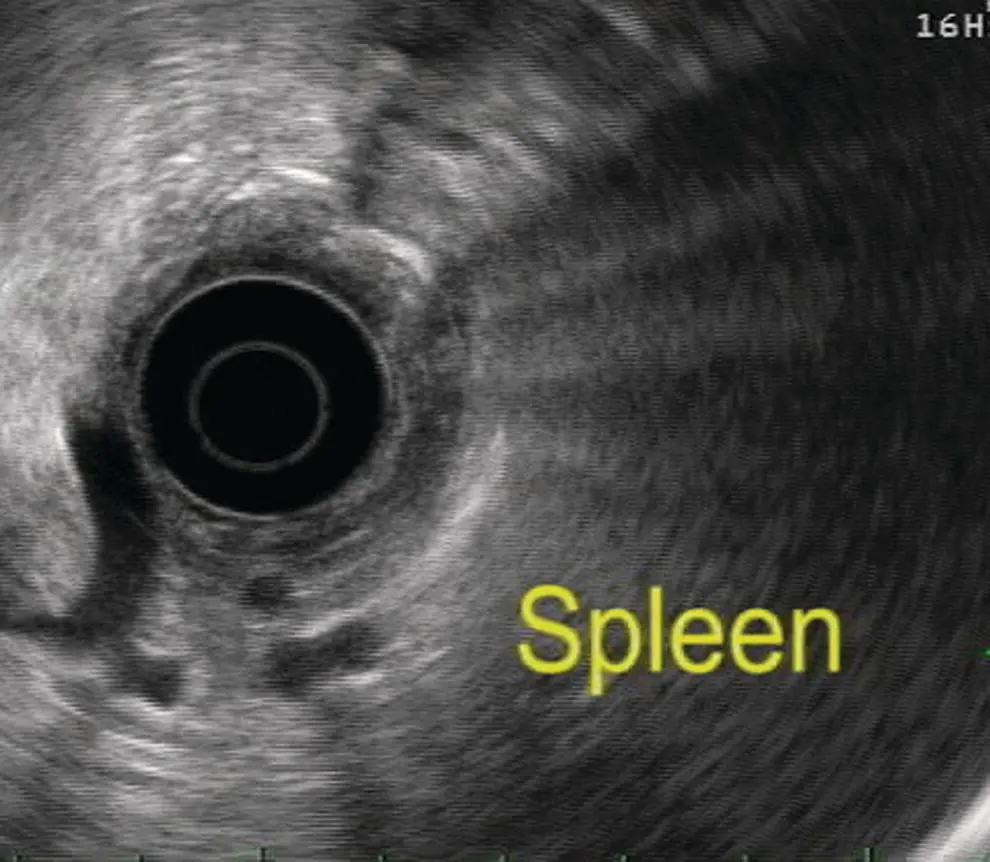

Spleen

The spleen appears as a homogeneous structure seen between the tail of the pancreas, left kidney, and gastric wall. With a radial scope it is imaged from the gastric cardia. It is similar to liver in echogenicity except that it is devoid of any ducts and vessels ( Figure 7.4). It can be easier to follow the splenic vein after visualizing the pancreas from the gastroesophageal (GE) junction. The splenic artery, splenic vein, renal vein, and the left adrenal are usually visualized as well while attempting to scan the spleen. The splenic vein can be easily traced along the inferior aspect of the body and tail of the pancreas; however, the splenic artery is tortuous and it is difficult to follow its course to the celiac trunk. With a linear scope one has to scan inferior to the left kidney and laterally to visualize the spleen ( Figure 7.5).

Figure 7.4 Image of spleen by radial ultrasound.

Figure 7.5 Image of spleen by linear ultrasound.